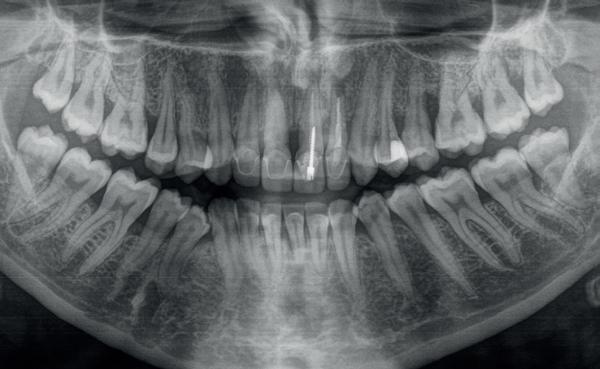

De patiënt, een 70-jarige man, had in het verleden tandheelkundige zorg ontvangen die zich kenmerkte door een ad hoc benadering. Er was geen sprake van een overkoepelend behandelplan of lange termijnvisie. De patiënt had naar eigen zeggen jarenlang niets

1. Studiofoto intake

aan zijn gebit gedaan behalve pappen en nathouden. Tandheelkundige zorg werd enkel verleend wanneer er zich een probleem voordeed (afbeelding 1, 3, 5).

De diagnose luidde lokaal parodontitis met ernstige furcatie aandoeningen; Stadium IV (vergevorderd); graad C (snel progressief) (afbeelding 7) De elementen die niet te behouden waren, werden geëxtraheerd.

5. OPT intake